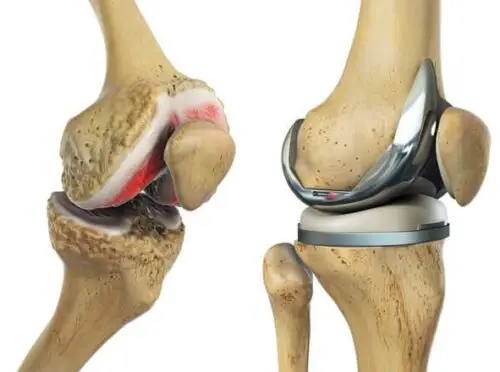

- يقوم الطبيب بإجراء شق في الركبة للوصول إلى المفصل المتضرر، بعد ذلك يبدأ الطبيب في إزالة الأنسجة والأربطة المتضررة ثم يبدأ في استبدال المفصل التالف بآخر صناعي.

- بعد ذلك بقوم الطبيب في تثبيت المفصل الجديد.

ما هي أنواع مفصل الركبة الصناعي ؟

هناك عدد من أنواع مفاصل الركبة الصناعية، وذلك لتتناسب مع الأشخاص، ومن هذه الأنواع ما يلي:

- مفصل معدن على بلاستيك: يعتبر هذا النوع من المفاصل الأقل سعر في الفئة الخاصة به كما أنه يعيش مدة طويلة ولكن مشكلته الوحيدة أن بعض الأجسام لا تستجيب معه.

- مفصل سيراميك على بلاستيك: يلجأ له الأطباء في العادة عند يكون المريض متحسس من المعدن.

- مفصل سيراميك على سيراميك: وعادة ما يكون مريح وسلس ولكن عيبه الوحيد أنه يصدر أصواتا عند المشي.

- معدن على معدن: يعتبر أقل أنواع المفاصل استخداما وهذا للمخاوف من تسرب المعدن داخل الجسم مما قد يؤثر بالسلب على باقي الأنسجة.